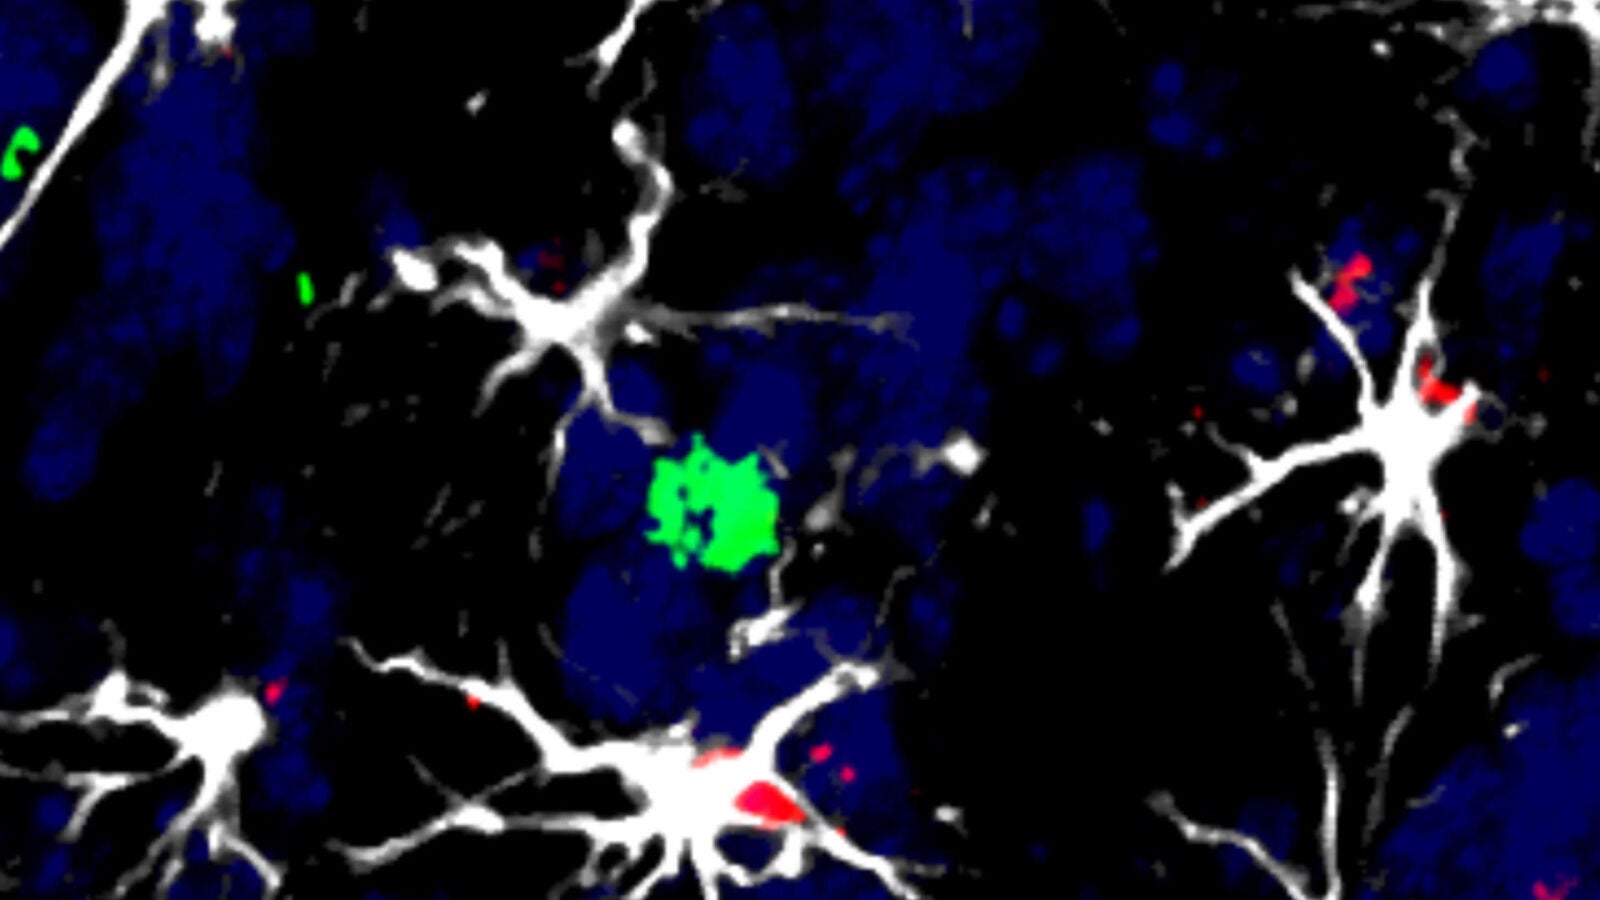

Concretamente, han identificado unas células cerebrales llamadas astrocitos que dificultan el trabajo del sistema inmunológico y le impiden matar las células tumorales.

"Los astrocitos pro-tumorales producen una molécula llamada TIMP1 que interviene en la inhabilitación de las células defensivas que deberían acabar con las células cancerígenas", señala otra de las autoras, la investigadora del CNIO, Neibla Priego.

"Hasta ahora no se había considerado a los astrocitos como inmunomoduladores, ni en estudios generales ni, desde luego, en relación con los tumores cerebrales. Nuestra investigación no es solo innovadora desde el punto de vista clínico, también lo es, y mucho, para el avance del conocimiento científico", subraya Valiente.

Una vez demostrado que esa molécula, TIMP1, actúa sobre las células del sistema inmunitario y las hace más ineficaces, el equipo del CNIO propone usarla como biomarcador, para detectar metástasis cerebrales afectadas por este mecanismo de inmunosupresión.